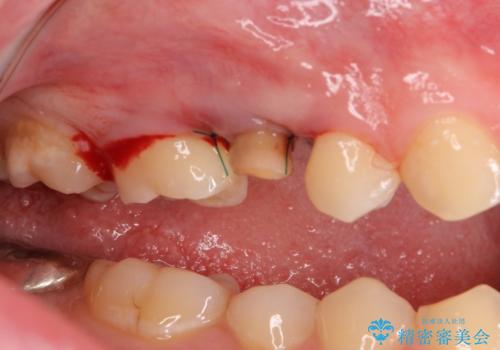

右上の被せものを除去したところ、中で歯が割れていたため、部分矯正で引っ張り出すことになりました。

歯を引っ張り出したり、歯肉の手術の経過待ちの間に、患者様のご希望で他の歯の虫歯治療も行いました。

・十分に引っ張り出した後、歯肉の手術が必要となります。